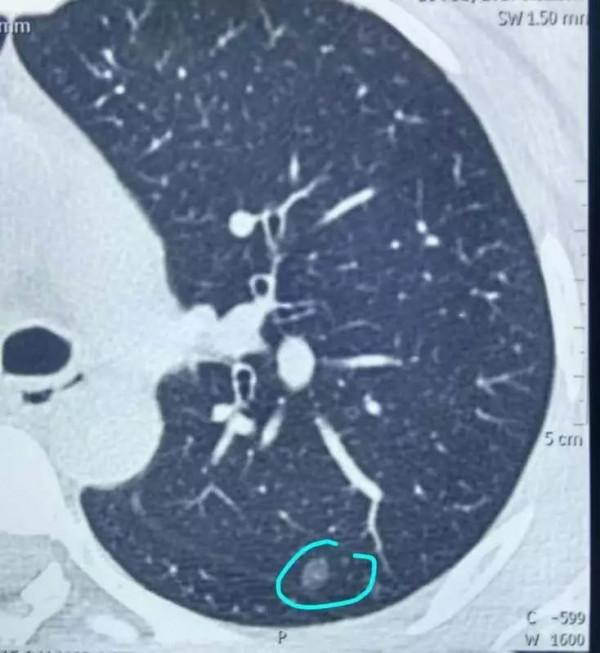

▲ CT片子上面,劃個小圈的那個小點就是肺小結節。

王濤表示,肺部結節的性質多種多樣,臨床中一般認為,如果肺部的結節小於8毫米、邊緣清楚光滑的,那麼考慮良性的可能性比較大,但仍需要定期隨訪。

一般來說,早期的結節生長都是非常緩慢的,如果結節在短時間內快速增大,則不能排除是惡性的。

大多數結節在兩年內未觀察到生長,一般可視為良性或是發展很緩慢的肺癌,建議每年複查。